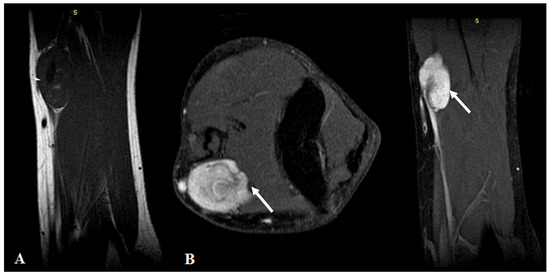

| Manole et al./2022 | US | First-line imaging tool |

| - detection and characterization | ||

| - assessment of the vessel | ||

| - follow-up | ||

| MRI | Second-line imaging tool | |

| - boundaries and relation with surrounding structures | ||

| - +/−invading features | ||

| - soft tissue edema | ||

| - distant metastasis |